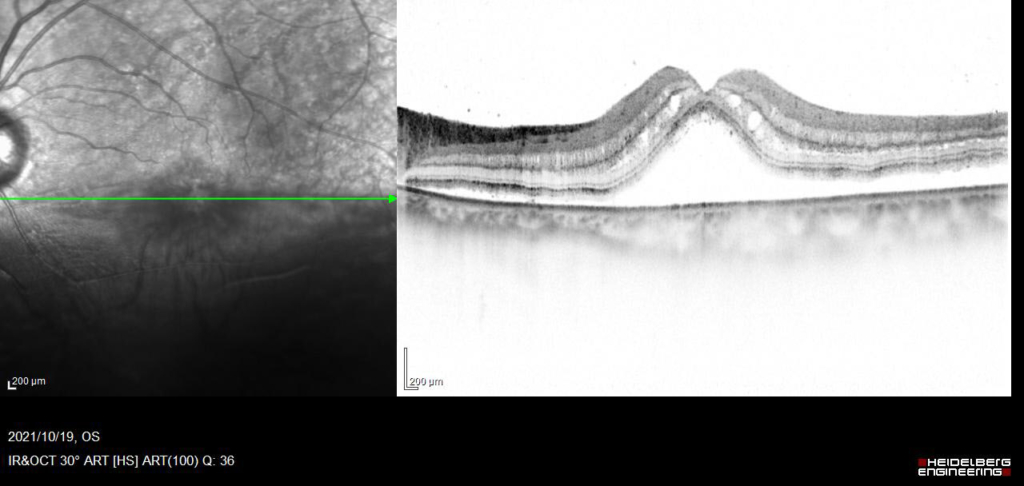

中心窩を含んで網膜剥離があり、外網状層の浮腫と嚢胞様変化がみられる。